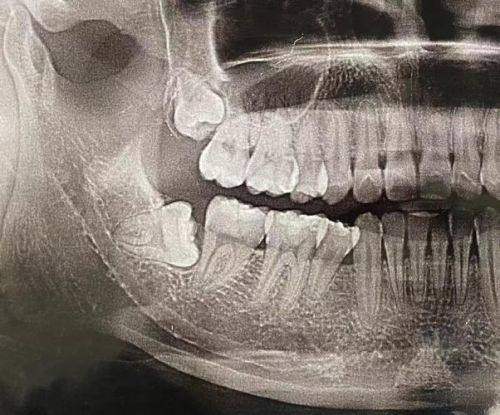

设备方面,都是从正规渠道购买的,是市场上主流的口腔设备。这些设备能提供更精细的检查服务,给医生诊断提供可靠依据,还能提高咱们就诊的舒适度和速度。